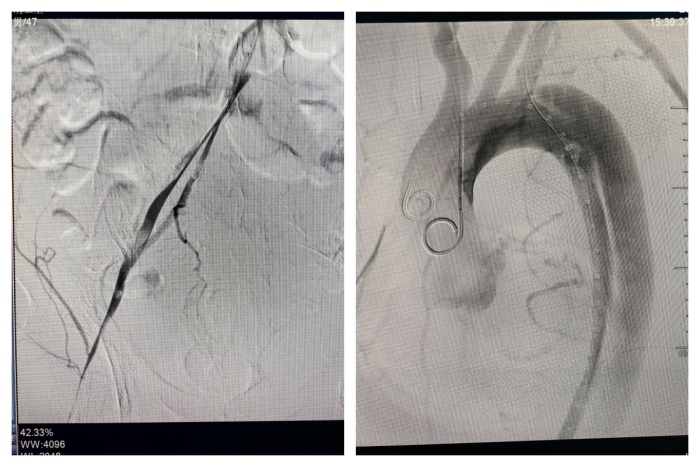

(图片1:外院CTA:消失的左髂动脉血管)

这位病友名叫胡某,年仅47岁。10小时前,因左下肢活动障碍而前往当地县医院就诊。经过初步检查,医生怀疑是脑卒中并进行了血管造影检查,但最终确诊为主动脉夹层和左下肢缺血。这一诊断结果让胡某的病情变得更加危急,因为如果处理不当,可能会出现主动脉夹层破裂致死或左下肢缺血严重到需要截肢的地步。由于当地县医院的救治条件有限,立即与南溪山医院启动了联合救治系统,将胡某转至该院进行进一步救治。